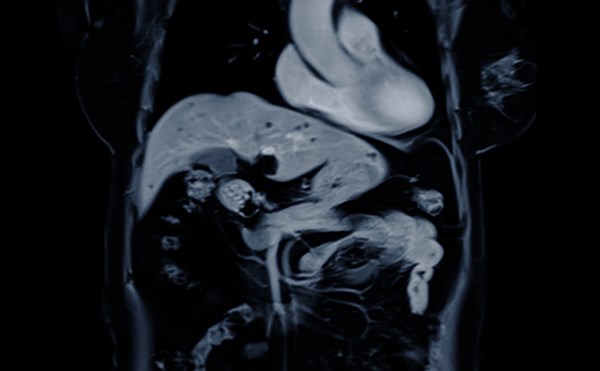

Altered Mental Status in an Infant

10 month old male infant presents to the ED by EMS with vomiting and altered mental status (AMS).